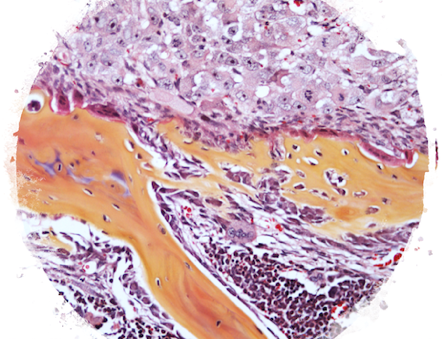

By studying how Nf1 loss-of-function impacts the maturation and function of chondrocytes and osteoblasts, we seek to understand the etiology of the most problematic skeletal maladies associated with neurofibromatosis type 1 (NF1), which includes dystrophic scoliosis, tibia bowing and recalcitrant bone healing.